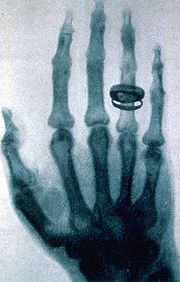

skeleton hand

X-Ray of Röntgen’s wife’s hand, her wedding ring is perfectly displayed.